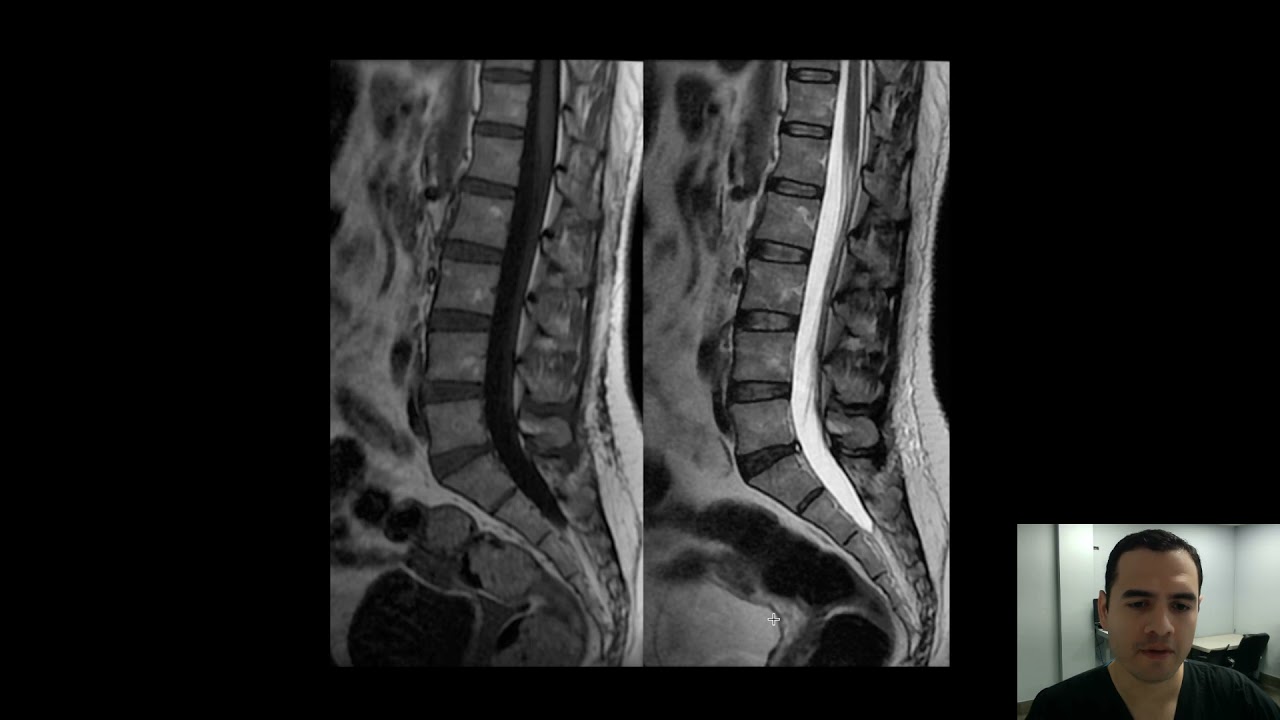

Ahora que tenemos una idea clara sobre los cortes, es hora de hablar sobre las imágenes T1 y T2. ¿Alguna vez has notado cómo algunas fotos pueden parecer más vibrantes que otras? Lo mismo ocurre en la resonancia magnética. Las imágenes T1 y T2 se diferencian en cómo se comportan los tejidos cuando se les aplica un campo magnético y ondas de radio. En una imagen T1, los tejidos ricos en grasa aparecen más brillantes, mientras que en una imagen T2, los líquidos, como el agua, son los que destacan. Esto significa que cada tipo de imagen tiene su propia utilidad en el diagnóstico. Por ejemplo, si un médico está buscando inflamación, probablemente utilizará una imagen T2, ya que el líquido inflamatorio aparecerá más brillante.

La diferencia entre T1 y T2 puede parecer confusa al principio, pero es crucial para el diagnóstico. Imagina que estás tratando de encontrar un tesoro escondido. La imagen T1 es como un mapa que te muestra las áreas ricas en recursos, mientras que la T2 te muestra dónde podría haber agua, lo que podría indicar un lugar húmedo o encharcado. Entonces, si un médico está buscando una lesión en un músculo, la imagen T1 puede ser más útil, mientras que si está buscando edema o líquido en una articulación, la T2 será su mejor aliada.

Ahora bien, es posible que te preguntes, ¿cuándo se utilizan estos cortes en la práctica clínica? La respuesta es: ¡en casi todos los estudios de resonancia magnética! Dependiendo de la condición que se esté evaluando, los radiólogos elegirán el tipo de corte que mejor se adapte a la situación. Por ejemplo, si se sospecha de una hernia de disco, un corte sagital puede proporcionar una visión más clara de cómo el disco se está desplazando y afectando a las raíces nerviosas. Por otro lado, si hay una preocupación por una masa en el abdomen, los cortes axiales son ideales para evaluar su tamaño y forma.

Como todo en la vida, los cortes sagitales y axiales tienen sus ventajas y desventajas. Por un lado, los cortes sagitales son excelentes para evaluar la alineación de estructuras, como la columna vertebral. Sin embargo, pueden no ser tan efectivos para visualizar ciertas patologías en el abdomen. Por otro lado, los cortes axiales son ideales para estudiar el abdomen y el tórax, pero pueden perder algunos detalles en la evaluación de la columna. Es como elegir entre dos herramientas: cada una tiene su propósito, y la elección depende de la tarea que necesites realizar.